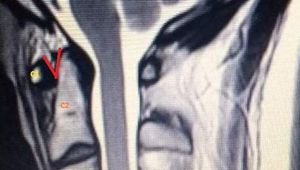

Another X-Ray shows the problem with his skull

"A catastrophic consequence of the EDS is CCI where the skull becomes unstable and begins to shift on the top of the spine - in my case, it is not an exaggeration to say that my head is quite literally falling off.

"My head no longer sits safely on my spine, and it is crushing vital structures like my brainstem and upper spinal cord.

An X-Ray of Connor Edward's skull shows a lateral overhang